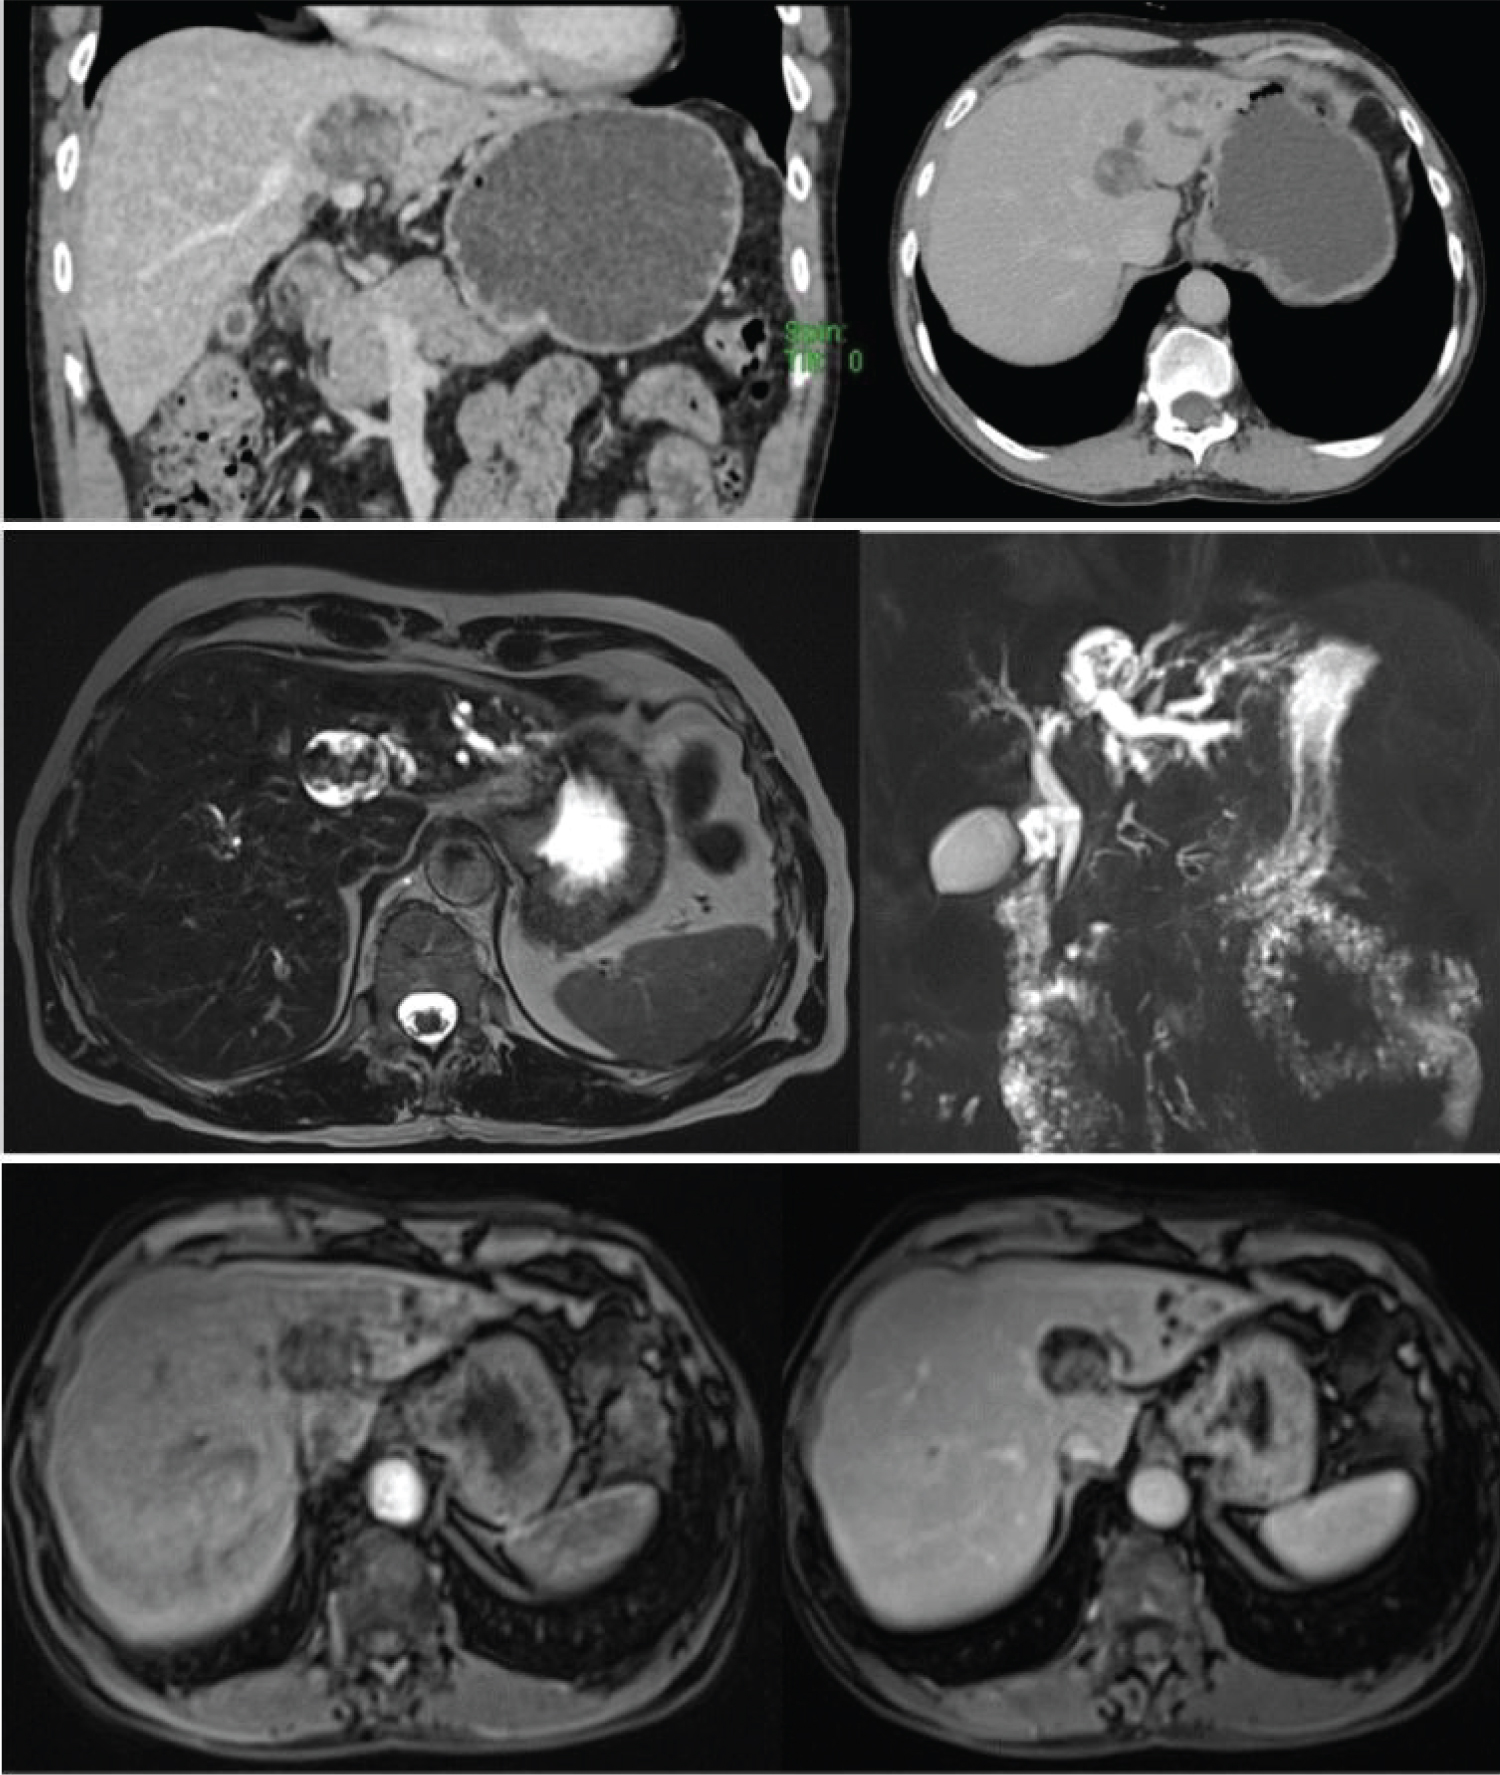

Our patient is an elderly female who presented with features of obstructive jaundice and upper abdominal pain for one month. Lab parameters were suggestive of obstructive pattern of jaundice and CECT is taken to rule out malignancy. CECT shows ill-defined heterogeneously hypo-enhancing lesion seen involving the medial aspects of segments 2/3 with upstream biliary radicle dilatation in the segments 2 & 3. In MRI, lesion appears T2 hyperintense, T1 hypointense with no diffusion restriction (Figure 4). Since the imaging findings were not very typical of cholangiocarcinoma, other possibilities were considered and screened for serum IG G4 levels which came out to be in high range. Then then patient was started on steroids and patient improved clinically with resolution of jaundice.

Figure 4: Inflammatory pseudotumor. (a,b) CECT axial sections show an ill-defined heterogeneously hypo-enhancing lesion seen involving the medial aspects of segments 2/3 with upstream biliary radicle dilatation in the segments 2 & 3. Geographic fat attenuating area involving caudate lobe and segment 4 of liver; (c,d) MRI T2 FS (a) and T1 out of phase (b) axial sections shows ill defined T2 FS hyperintense and T1 hypointense lesion in the medial aspects of segments 2/3 of liver; (e,f) MRI DWI (e) and ADC (f) axial sections shows ill-defined lesion that appears hyperintense and isointense in the diffusion weighted and ADC images respectively, suggestive diffusion shine through. View Figure 4

Our patient is an elderly male who presented with abdominal pain and jaundice for two months. Lab parameters were suggestive of obstructive pattern of jaundice and proceeded with cross-sectional imaging to look for the cause. CECT shows cystic lesion in the segment 4 of liver with enhancing intra-cystic solid areas and upstream biliary radicle dilatation. In MRI, lesion appears to be in contiguity with left hepatic duct and intra-cystic solid areas appear T2 hypointense and hypoenhancing (Figure 5).

Figure 5: IPMN-B. (a,b) Contrast enhanced CT coronal (a) and axial section (b) shows a cystic lesion in the segment 4 of liver with enhancing intra-cystic solid areas. Lesion appears to be in contiguous with upstream dilated biliary radicles in the segments 2 & 3 of liver; (c,d) MRI-T2 SPACE 3D axial section shows T2 hyperintense cystic lesion with hypointense solid areas within the lesion and upstream biliary radicle dilatation. (b) MRCP images shows cystic lesion in continuity with left hepatic duct causing upstream biliary radicle dilatation; (e,f) Post contrast T1 VIBE axial sections shows hypoenhancing solid areas in the arterial phase (e) which progressive increase in enhancement in the portal venous phase (f). View Figure 5

A 7-month-old infant presented with the distended abdomen and failure to thrive noticed by the mother for two weeks. CECT shows a large lobulated mass seen arising from the left lobe of liver, which displays avid thick peripheral enhancement in arterial phase, persistent in the subsequent phases with necrotic areas. The mass lesion is supplied by the prominent left hepatic artery (Figure 6).

Figure 6: Hemangioendothelioma. Contrast enhanced CT axial sections shows a large lobulated mass seen arising from the left lobe of liver, which displays avid thick peripheral enhancement in arterial phase (a) which is persistent in the subsequent phases (b) with non-enhancing necrotic areas. The mass lesion is supplied by the prominent left hepatic artery. View Figure 6

Our patient is an elderly female patient who presented with abdominal pain, distension and jaundice for the past one month. On non-contrast CT- tumors are hypoattenuating compared to the surrounding hepatic parenchyma. On CECT, most lesions are hypoattenuating, some lesions can be hyperattenuating [25]. On T1-weighted images - hyperintense areas represent hemorrhagic areas. On T2-heterogenous intensity shows compartmentalization within the tumor. On T2 low intensity - hemosiderin, fibrous components. On T2 - high intensity - necrosis [25] (Figure 7).

Figure 7: Primary Hepatic Angiosarcoma. Plain (a) and contrast enhanced CT (b) axial sections shows heterogeneous density lesion with necrotic areas and hemorrhagic foci within seen arising from spleen. Similar appearing lesions seen involving both lobes of liver. No significant post-contrast enhancement seen within the lesion. View Figure 7